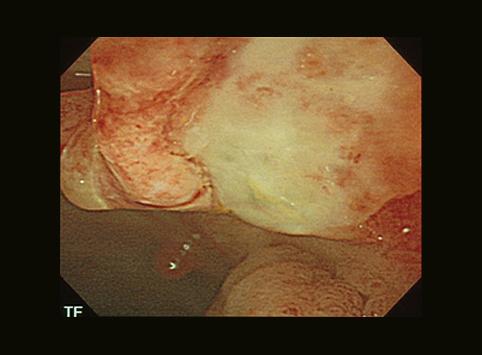

疾病(病理主体)的分类恶性上皮肿瘤/其他

部位(按器官分)大肠/降结肠

检查方法内窥镜

肿瘤的肉眼分类0型(表在型)/IIa型(IIa+IIc)

肿瘤最大直径15~19

肿瘤的深度sm